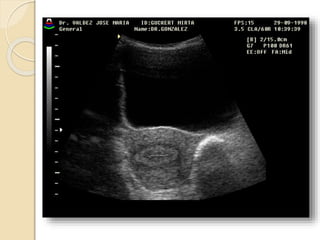

Quistes Funcionales

Quistes foliculares:

Resultan de una falla en la involución.

El folículo se distiende y mide mas de

30mm de diámetro. No dan síntoma a

menos que adquieran mucho tamaño y

sufran ruptura, torsión o hemorragia

Cuerpo lúteo quístico:

Esta dado por una hemorragia exagerada

en un folículo que ovuló y esta en etapa de

regresión.

Frecuentemente son asintomáticos.

Ambos quistes funcionales se resuelven en

dos o tres ciclos.